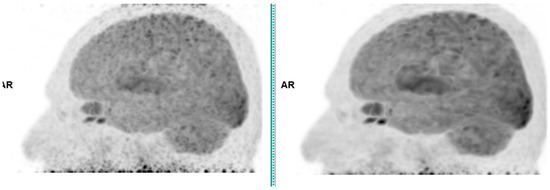

Across the three radiotracers, the AI-denoised images demonstrated a significantly improved performance in the visual analysis compared to conventional PET images. AI-denoised images were rated as interpretable (scores of 3–5) in all cases, compared to 65% for conventional images. Furthermore, an excellent image quality (score of 5) was achieved in 85% of all AI-denoised images, a significant improvement compared to the 50% in standard acquisitions. SubtlePET™ processing resulted in consistently lower noise levels, particularly for 18F-FDG scans, where 85% of images scored 4 or 5 for noise reduction compared to 60% in conventional scans. Lesion detectability was maintained or enhanced across all radiotracers, ensuring no compromise in the diagnostic accuracy. For 18F-FDOPA, a tracer with inherently lower signal-to-noise ratios, the AI algorithm improved the detection confidence by 25% compared to standard protocols. The visual comparison is illustrated through different MIP images and transaxial images (Figure 1, Figure 2, Figure 3 and Figure 4)

For 18F-FDOPA

For the 18F-FDOPA PET, which is inherently more susceptible to background noise due to a lower tracer uptake in certain brain regions, the SubtlePET™ processing significantly boosted the image quality. The SNR increased from 10.1 to 16.8, and the CNR improved from 4.9 to 8.1, facilitating improved visualization of the focal dopaminergic uptake in the basal ganglia and potential neoplastic lesions in the pancreas and adrenal glands. These enhancements are particularly valuable for interpreting subtle neuroendocrine abnormalities where a high image contrast is essential.

Figure 4. Total body 18F-FDOPA PET CT, MIP and transaxial images (left: without AI denoising; right: with AI denoising).